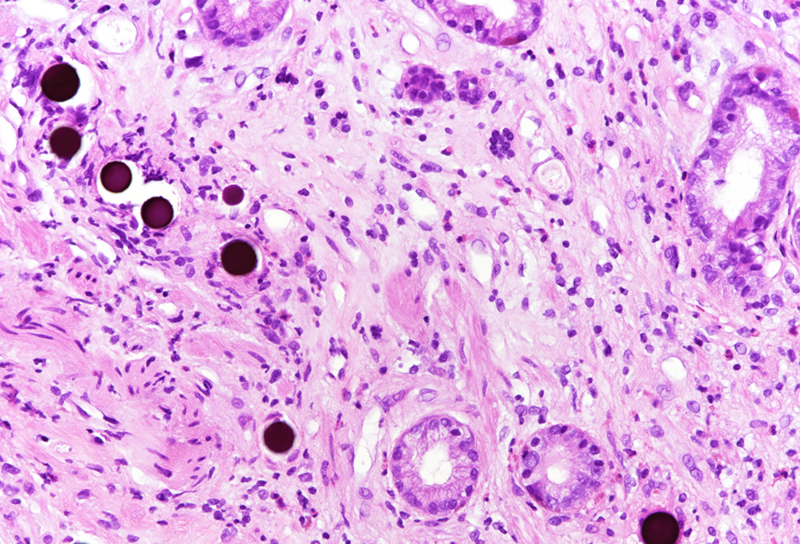

Histologically, in the duodenal bulb and all gastric biopsies was visible a blueish spherical foreign material in the stroma, inside small blood vessels, which corresponded to the given chemoembolization medium – yttrium-90 microspheres. Surface mucosa of all samples showed reactive and inflammatory changes with atrophic areas (Panels A-D).

Selective internal radiation therapy (SIRT) is increasingly used for the treatment in non-resectable primary or secondary liver malignancies by injecting intra-arterially radioactive yttrium-90 microspheres. However, due to rich vascularisation of the liver and surrounding organs, migration of microspheres is possible, leading to complications. The most common complications are involving GI tract – gastritis, gastrointestinal ulcers, cholecystitis and liver disease, and non-GI - radiation pneumonitis. That is why awareness of these complications and multidisciplinary approach are necessary for patient’s overall well-being. The pathophysiological mechanism behind gastric injury is not fully understood, but seems to be due to chronic and persistent ischemic injury to the mucosa of the stomach, leading to ulceration and inflammation in the viable mucosa. Please note that reactive cytological and nuclear changes may be marked, thereby mimicking dysplasia (a dangerous caveat).